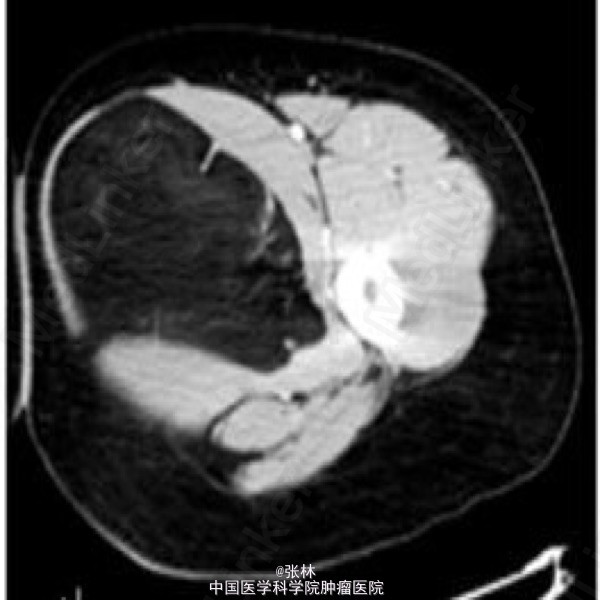

发现左大腿肿物1年,近来肿物明显增大。查体:大腿内侧见一肿物隆起,边界欠清,质中偏软,无明显搏动感,无压痛。

相当于股骨上段平面,大腿内侧肌群内见异常类圆形低密度影,边界清晰,边缘有中等密度线状分隔影伸向瘤内,增强后未见强化。

【诊断】脂肪瘤(病理确诊)。镜下见送检脂肪组织有大量成熟脂肪细胞,大小和形态不完全一致,瘤细胞排列紧密,并可见少量的纤维组织包被。

【讨论】 脂肪瘤(lipoma)是一种由成熟脂肪细胞构成的肿瘤,常有一薄层纤维包膜,呈扁平或分叶状,边缘清楚,包块质软。镜下见成熟的脂肪细胞堆积,其间有不规则纤维组织分隔。 本病发生于含有脂肪组织的全身任何部位,但多见于颈、肩、背、臀及肢体的皮下组织和腹膜后。亦可见于肠系膜、肾周、肌肉和筋膜下。皮下脂肪瘤发展缓慢,大小不一,大者可达10~20kg。表面皮色正常,包块质软。 影像诊断要点:X线表现为边缘规整、清晰的低密度区,而且随肌肉收缩其形态可发生变化。肿瘤越大,透光度相对越强。肿瘤内可发生不规则钙化。CT平扫肿瘤呈一个或多个边缘光整的极低密度区,多呈圆形或分叶状。周围组织受压。CT值约为-120~-80HU,密度均匀,有包膜,内部可有分隔。增强扫描无强化。脂肪瘤MRI信号具有特征性,呈短T1中长T2信号,在所有序列中均与皮下脂肪组织信号相同,边缘清楚,信号强度均匀,部分有低信号分隔。 脂肪瘤影像学表现有其特殊性,一般无须与其他病变鉴别。